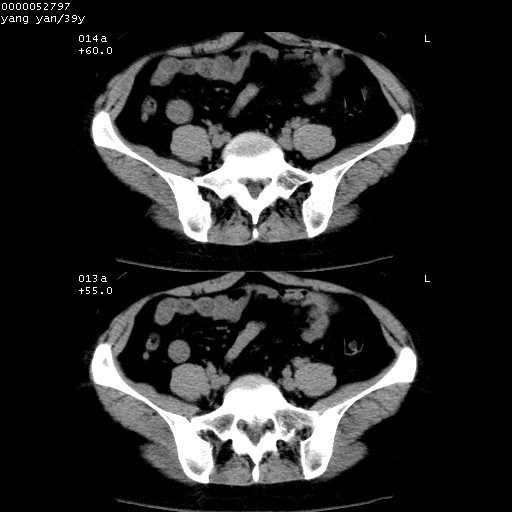

患者 女,39岁。因外伤检查,偶然发现。

典型!双侧骶髂关节致密性骨炎。

典型!病变主要累及双侧髂骨。常见于育龄期妇女。

致密性骨炎,一般不跨越关节面,可是这个骶骨关节面也有硬化。

髂骨致密性骨炎系一种以骨质硬化为特点的非特异性炎症,有高度致密的骨硬化现象,尤其以髂骨下2/3更为明显,但关节间隙则无改变。因位于骶髂关节,且该关节症状明显,故又称之为“骶髂关节致密性骨炎”。 本病90%以上为中年女性,以妊娠后期、尤其分娩后为多见,亦可见于尿路或女性附件慢性感染后,或盆腔内其他感染。此外,臀骶部的外伤亦可诱发或引起本病。  妊娠、分娩及外伤均可引起骶髂关节韧带的撕裂而易使局部的血供受阻。因此早期局部呈现充血、水肿及渗出增加等,渐而局部出现增生与变性反应,随着胶原纤维的致密化而向硬化演变;血管形成厚壁血管,易闭塞而引起髂骨耳状面处缺血和缺氧,骨质呈现硬化性改变,以致手术时局部出血较少。骶髂关节囊壁显示纤维增生、弹性降低及松动样改变。继发于盆腔内炎症者亦出现相类似的病理改变,可能系细菌内毒素作用所致。